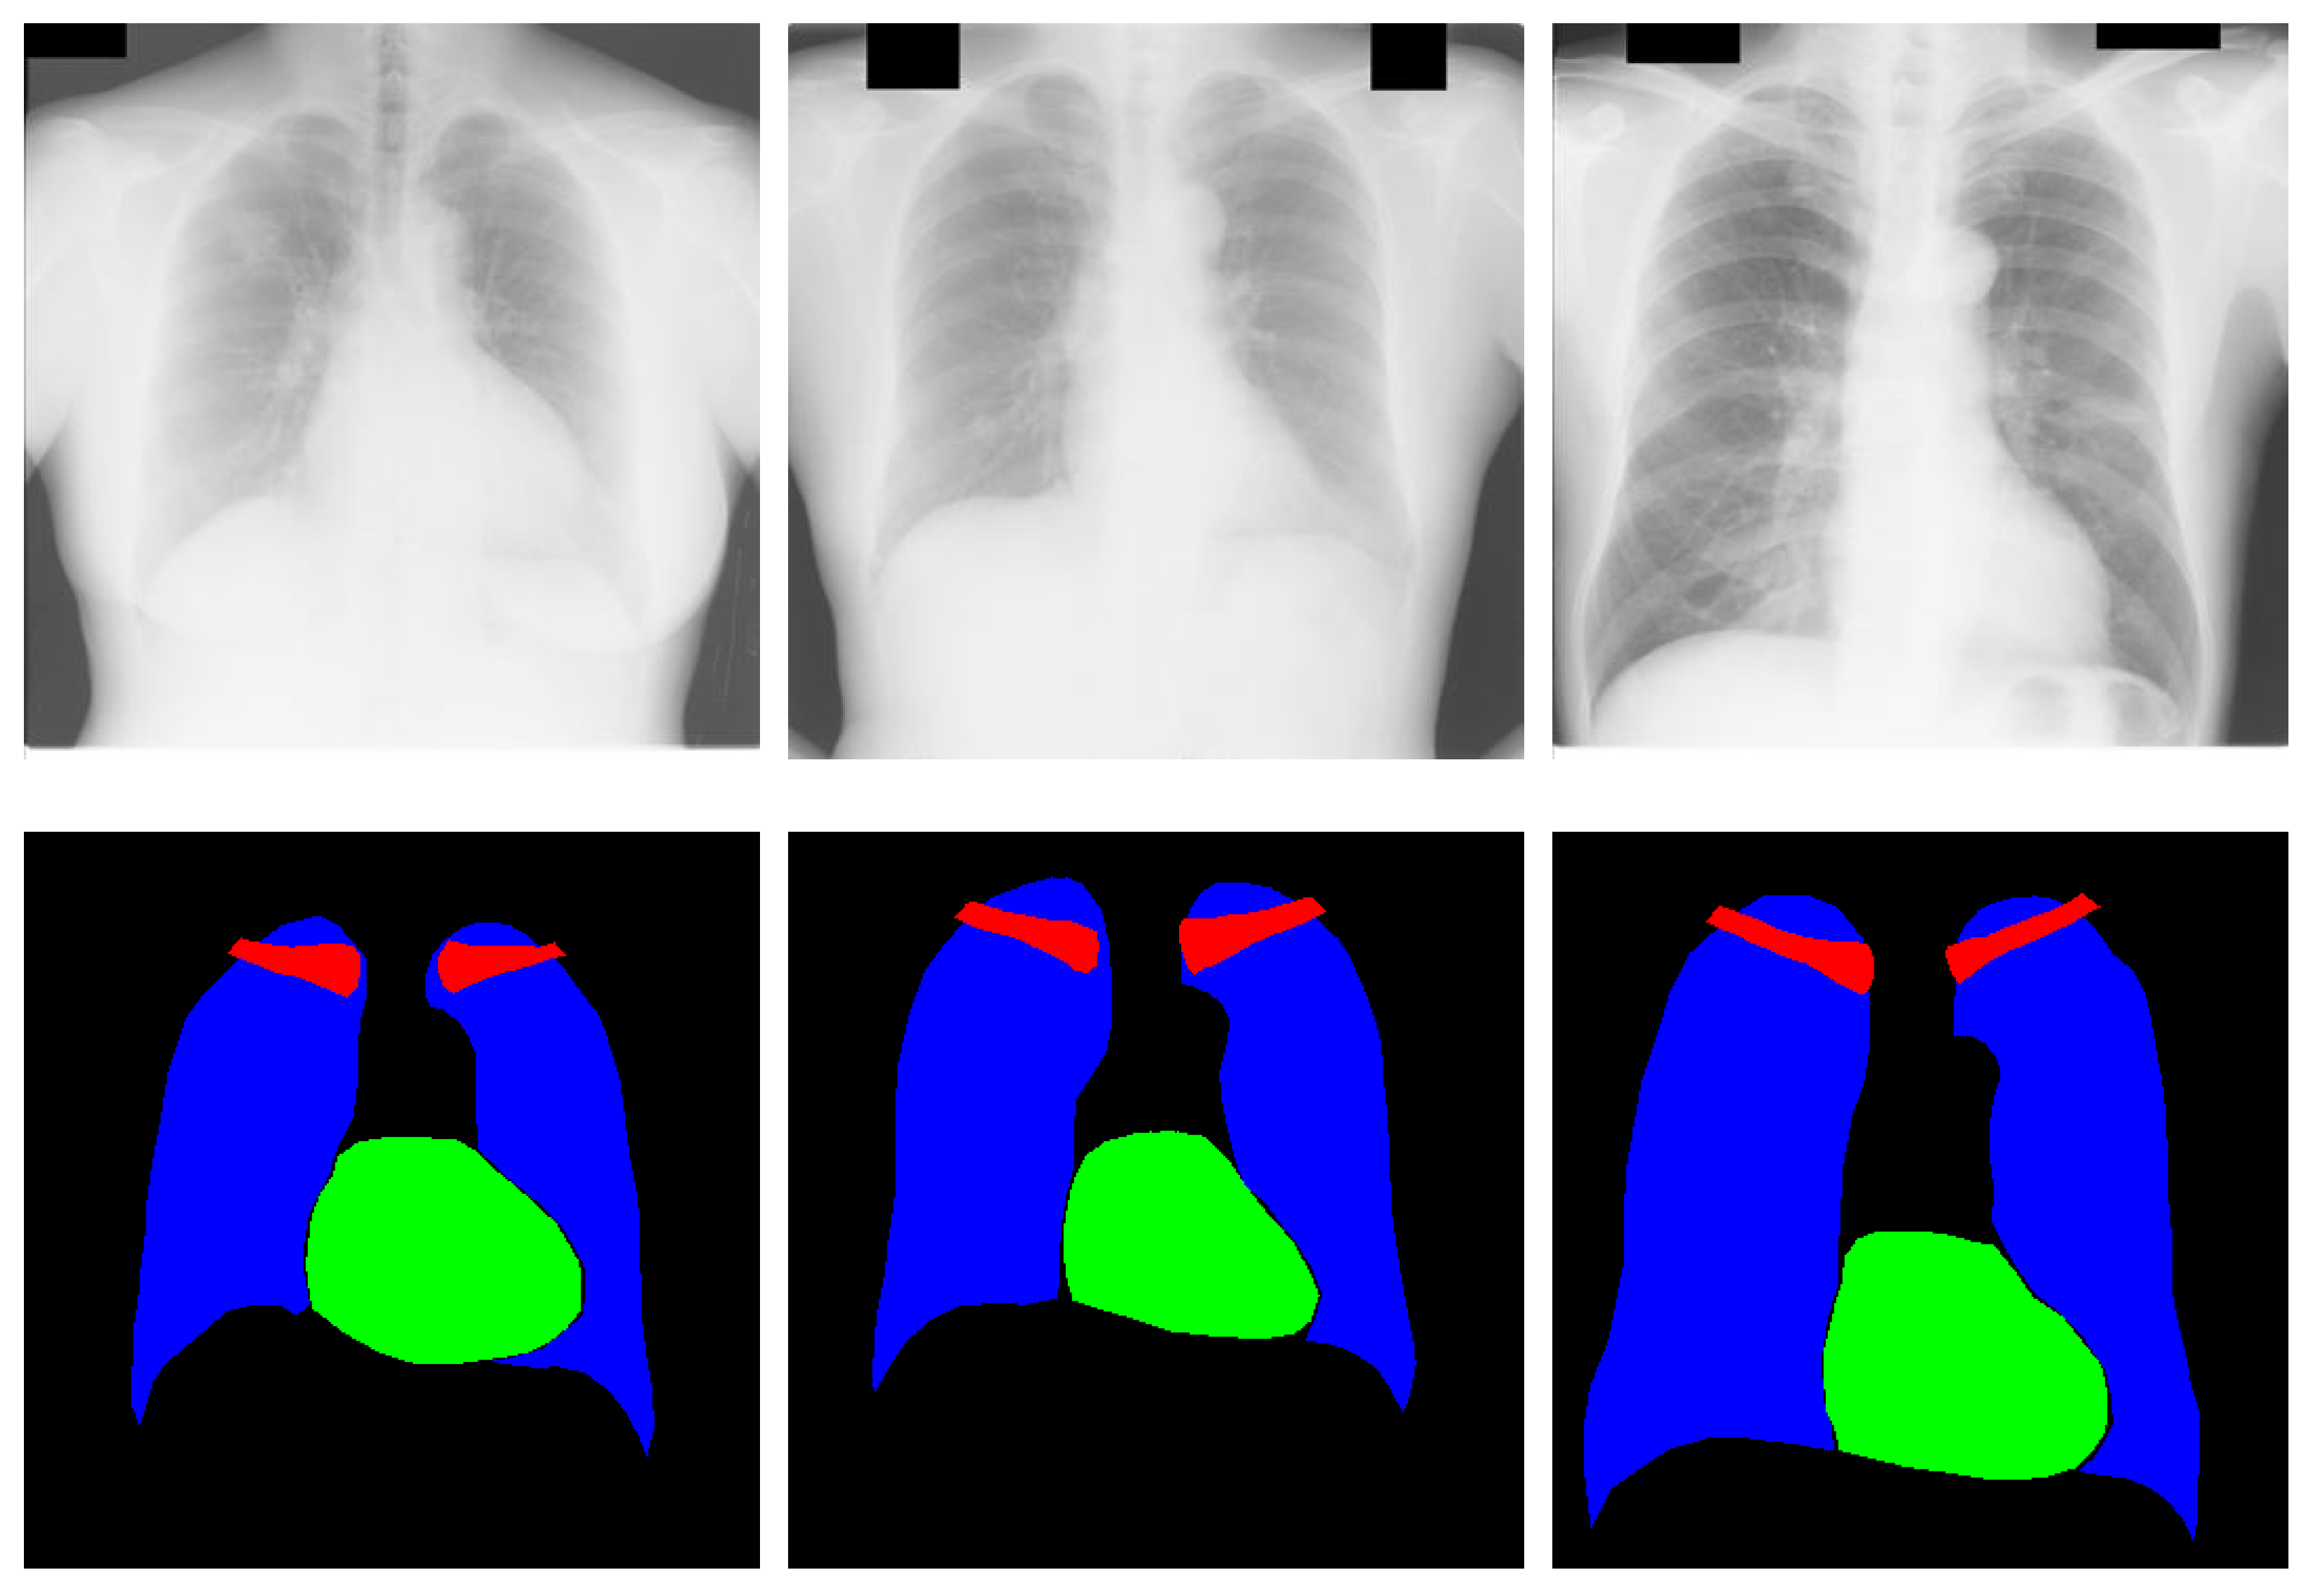

4.3.1. Chest Anatomy Segmentation Testing Using CardioNet